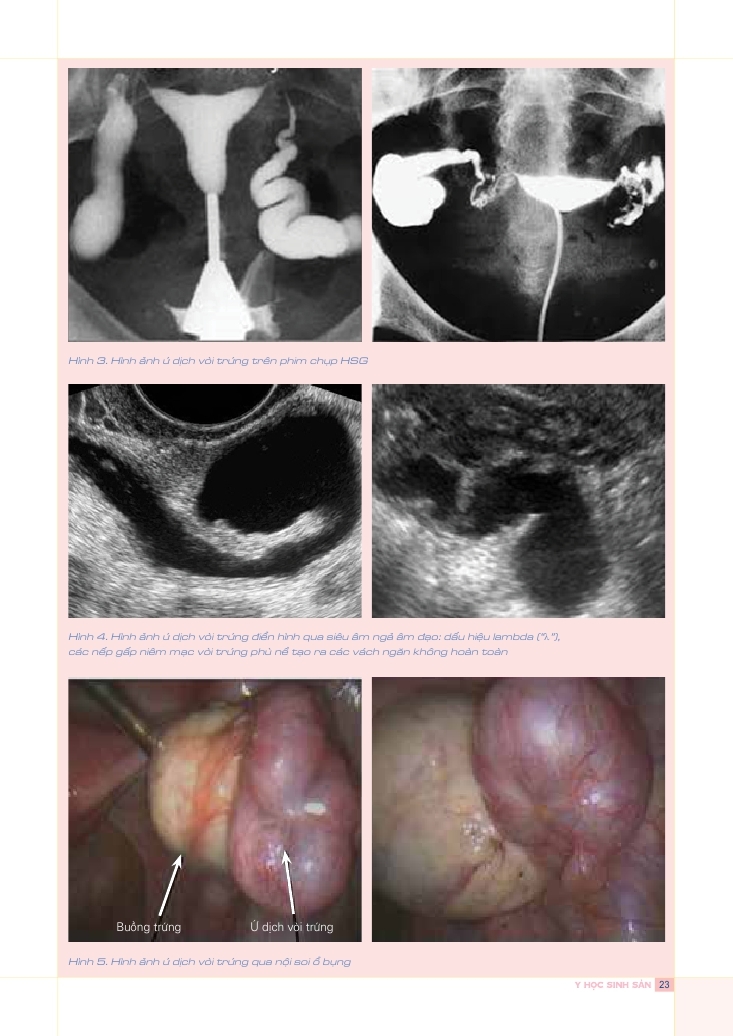

Ứ dịch vòi trứng